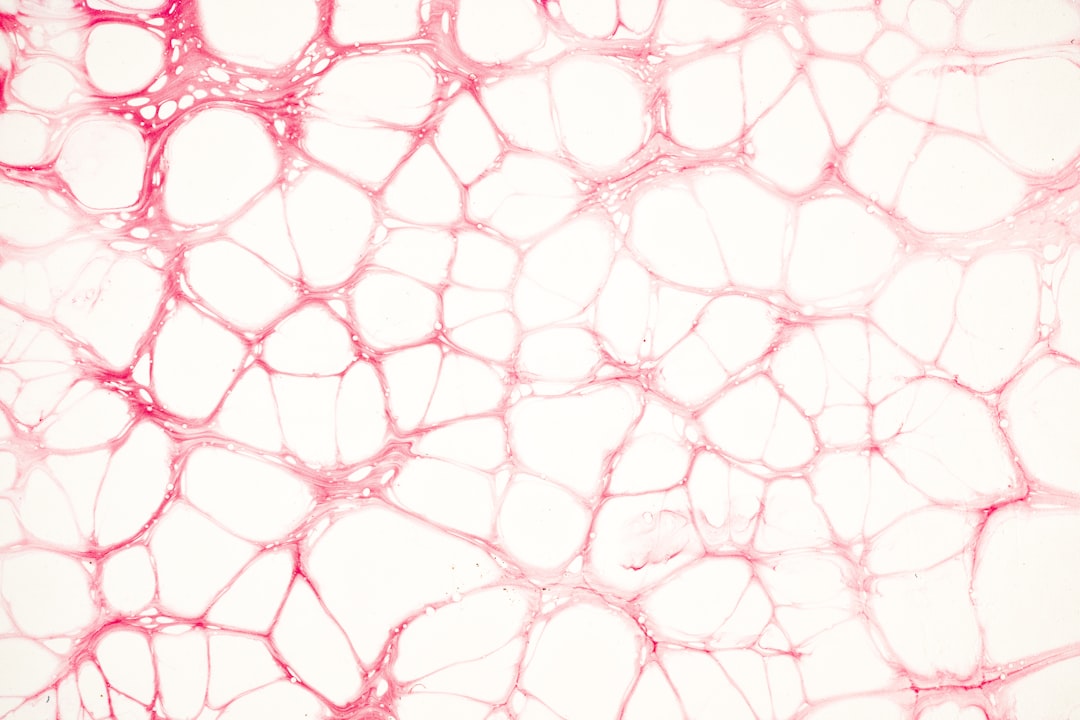

파이토프리콜라겐은 식물에서 추출한 콜라겐으로, 인체에 필요한 다양한 아미노산을 포함하고 있습니다. 일반 콜라겐과는 달리, 이 식물성 성분은 vegan 및 vegetarian 식단을 따르는 분들에게도 이상적인 선택입니다. 보통 피부, 관절, 근육 등에 긍정적인 영향을 미쳐, 많은 연구에서 그 효과를 입증하였습니다. 파이토프리콜라겐은 특히 피부의 탄력을 높이고 주름을 완화하는 데 도움을 줄 수 있습니다. 이렇게 많은 이점이 있는 성분에 대해 알고 넘어가면 좋겠네요!

첫 번째로 말할 수 있는 파이토프리콜라겐의 효과는 피부 건강입니다. 이 성분이 피부의 수분을 보충하고, 탄력을 늘려 주름을 완화시키는 데 있어 매우 효과적이라는 연구 결과가 있습니다. 예를 들어, 한 여성의 경우 3개월간 파이토프리콜라겐을 섭취한 후 피부의 윤기와 탄력이 현저히 개선되었다는 사례가 있습니다. 이러한 변화는 자연스러운 노화 과정을 지연시킬 수 있습니다.